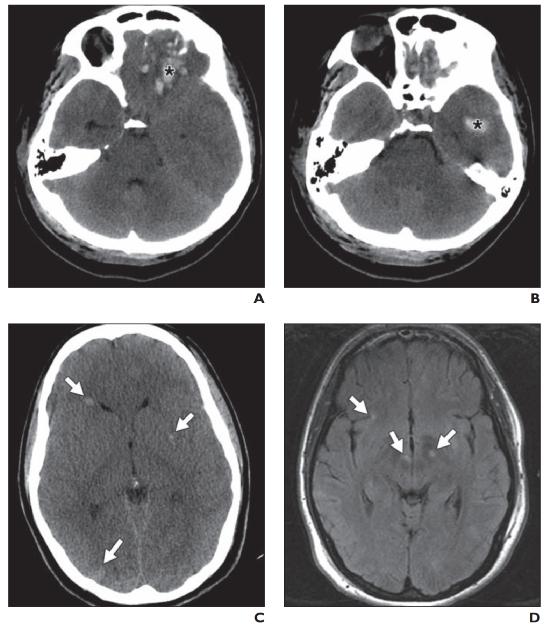

在 CT 上,小血管缺血性疾病表现为小穿支动脉区域皮质下和脑室周围白质的多发性白质低密度影。基底神经节和幕上区域也可见局灶性腔隙(图 5A )。高血压患者常见的自发性出血,一般位于基底节或丘脑。在存在败血症或先天性心脏病的情况下,栓子也会在血管区域之间的边界处产生分水岭梗塞。MRI 显示缺血区域在 T2/FLAIR呈现 高信号(图 5B ))。扩散受限存在于急性期,但在亚急性期和慢性期正常化。

其他微血管病大脑受累的分布不同。在淀粉样血管病中,多灶性和脑叶出血性中风很常见。GRE/磁敏感加权成像可用于检测隐匿性微出血病灶(图6A 、 6B, 和6C)。

图 5A——小血管缺血性疾病。半卵圆中心水平的平扫 CT 图像显示弥漫性皮质下白质低密度以及代表腔隙的更多局灶性低密度(箭头)

图 5B —小血管缺血性疾病。FLAIR 图像显示多个脑室周围高信号灶。

图 6A—淀粉样血管病。未增强 CT 图像识别出以右侧基底神经节为中心的急性出血(星号),提示高血压原因。血肿被血管源性水肿的薄边缘包围并延伸到右额角。两额叶出现慢性脑软化灶(箭头)。

图 6B—淀粉样血管病。T2 加权 MR 图像显示出血区域(星号)周围有磁敏感伪影,周围水肿呈高信号。两个枕角也有出血液平(箭头)。

图 6C —淀粉样血管病。T2 *加权梯度回波 MR 图像再次显示右额角(星号)急性出血。整个脑实质和脑沟(白色箭头)有多个病灶,表示慢性微出血和浅表铁质沉着症。右额叶有局灶性脑软化(黑色箭头),与 CT 所见一致。